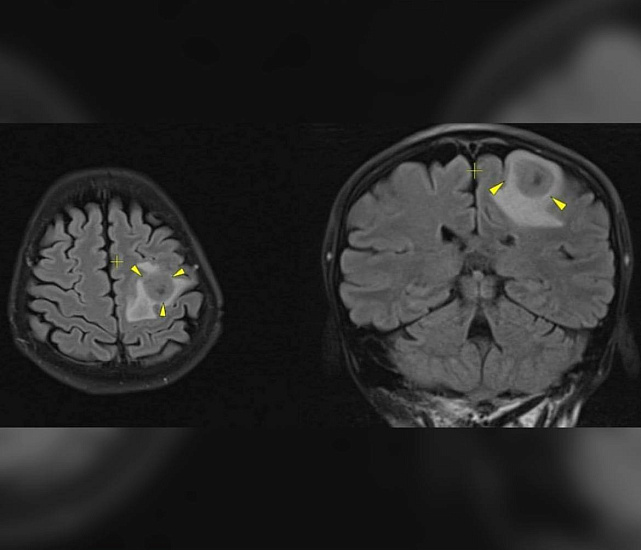

Диагностика показала наличие метастатических процессов с первичным очагом в грудной клетке. Это образование и было причиной болей. Результаты биопсии подтвердили лейомиосаркому.